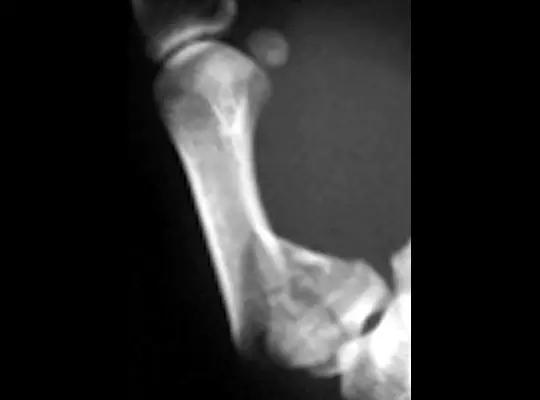

8. Mallet Finger/Baseball finger

即锤状指。远节指间关节的屈曲畸形,是由附着远节指骨伸肌腱分离引起,也可由伸肌腱的直接损伤继发引起。或由远节指骨撕裂性骨折引起肌腱嵌入骨折端引起。